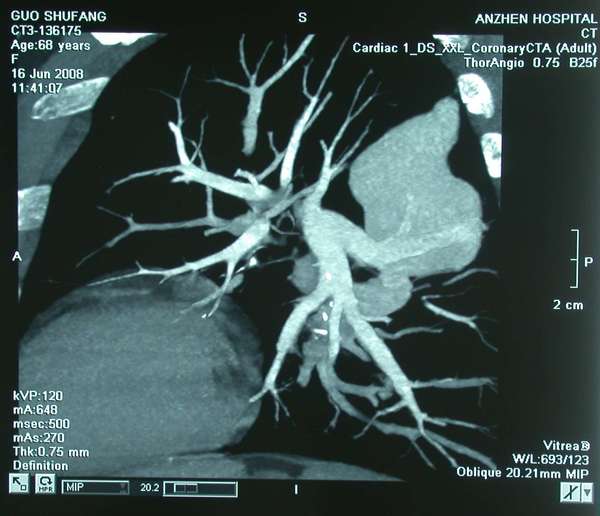

九、螺旋CT血管成像技术可从各个角度显示血管结构,准确性高,具有明显优势。优点:是无创检查,不需要插入导管。缺点是需要较长时间屏气,否则影响检查效果;对大的肺动静脉瘘空间分辨率差。

胸片、CT、造影均见:左肺下叶尖段及右肺右肺下叶后基底段各一圆形影,大小约2.5X2.5cm,边缘均清楚,均有粗大条状影通向肺门。符合双肺动静脉瘘。